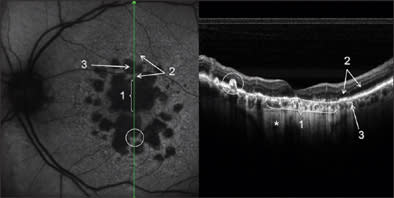

A 69-year-old woman had an 8-year history of dry age-related maculopathy in both eyes. Best-corrected VA in her left eye was 20/63. In Figure 3, we present images of simultaneous acquisition of AF and SD-OCT. The SD-OCT images make clear the difference in retinal layers between normal retina and atrophy. Two kinds of atrophic areas are distinguishable: the bigger one in which both photoreceptors and RPE layers are lacking; and the smaller one with an evident alteration of photoreceptors and RPE cells that are clearly dystrophic but still present.

Figure 3. Confluent and multiple retinal atrophic areas simultaneously examined by AF and SD-OCT (left eye). In the AF image, there is absence of autofluorescence in correspondence to RPE atrophy, due to the lack of lipofuscin. In the SD-OCT image, subretinal structures under atrophy are more visible for higher passage of reflectance, and it is possible to visualize the sclera (*). Note the differences in the RPE and photoreceptors layers between the normal retina (2) and atrophy areas (1 and 3). In the white circle, a hypertrophic RPE area can be seen.

In both cases, atrophy of the retina, as identified on OCT, explains the better visualization of subretinal structures. In particular, choroidal vessels are evident and their limits are sharper than under normal retina areas; even sclera could be visualized under choroidal vessels. Note that, along the scan line, there is an area of hypertrophic RPE area corresponding in retinal imaging to 1 of the residual autofluorescent zones surrounded by atrophy. In Figure 4, a comparison is shown between SD-OCT (top panel) and TD-OCT (bottom panel) images of the right eye. Best-corrected VA in this eye was 20/32 because of a relatively conserved neuroretina in the foveal region. The retina is diffusely thinned so that choroid and choriocapillaris are visible. Note the high backscattering (*) in correspondence of an atrophy area: In SD-OCT imaging, choroidal vessels are more distinguishable than in TD-OCT images.